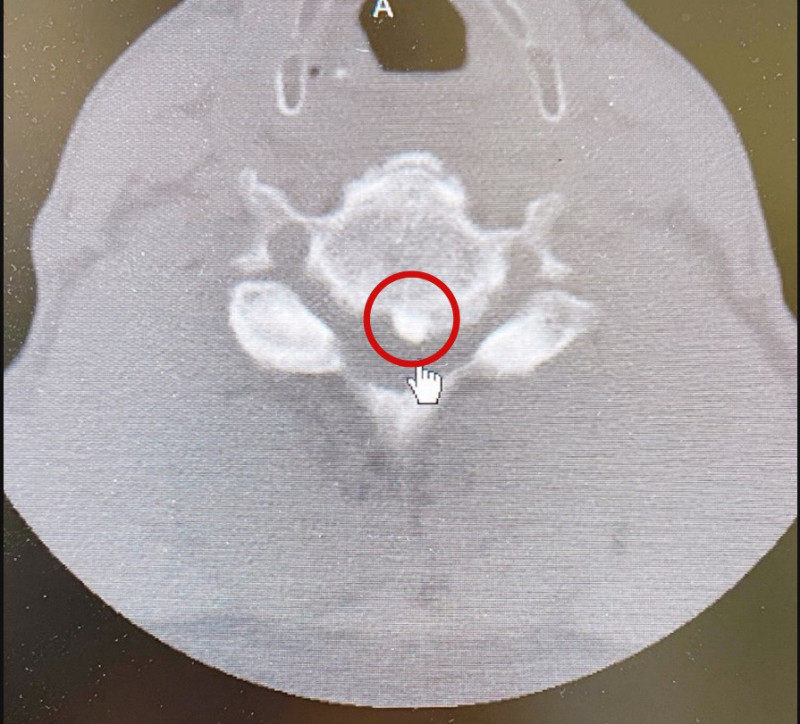

〔記者黃良傑/高雄報導〕60多歲男子1年多前雙手發麻無力,四處求醫,吃藥兼復健,效果卻不佳,2個月前雙腳出現麻痺無力,甚至走路不穩,趕緊求助中正脊椎骨科,經MRI磁振造影及電腦斷層檢查,發現他罹患素有「東亞隱形殺手」之稱的頸椎後縱韌帶骨化症,院長高振興表示,台灣人盛行率2.1%至3%,患者多無症狀,偶然健檢或脖子不舒服就醫才被發現。

該病患在2個月前雙腳麻木無力,走路不穩,才驚覺不對勁,透過檢查發現是頸椎後縱韌帶骨化症,竟骨化到如骨頭一般堅硬,甚至壓迫到脊髓神經,8月底,從嘉義輾轉到中正脊椎骨科接受治療,因6、7節頸椎處的後縱韌帶已骨化,壓迫到脊髓神經,導致他肢體緊繃、無力。

高振興表示,後縱韌帶骨化症若壓迫到脊髓神經,就必須手術治療,所幸僅短節段,從頸部前位手術把壓在神經的骨化韌帶切除,骨化節數多的病患,大多採後位頸椎減壓手術;骨化短節數的病人,可考慮從頸前位把壓迫神經的骨化韌帶切除固定或做人工椎間盤,這樣的手術困難度較高,但也因節數短癒後情形較好。